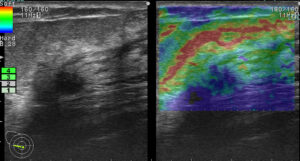

上に挙げた4つのエラストグラフィー

これが何を物語っているか?

エラストグラフィーは何か所見があった際に「これは怪しい!」と思わない限り追加で行わないものです。

これを実は4回も(昨年)行っていたのです。

つまり、(昨年も)その技師は「明らかに癌を疑っていた。」

この4枚のエラストグラフィーは技師の「これは怪しい所見です!是非要精査にしてください!」という心の叫びと言えるんだね!

まさに、その通り!

ただ、悲しいかな。技師さんのその「必死な思い」は、検診画像評価を行う医師には伝わらなかった。